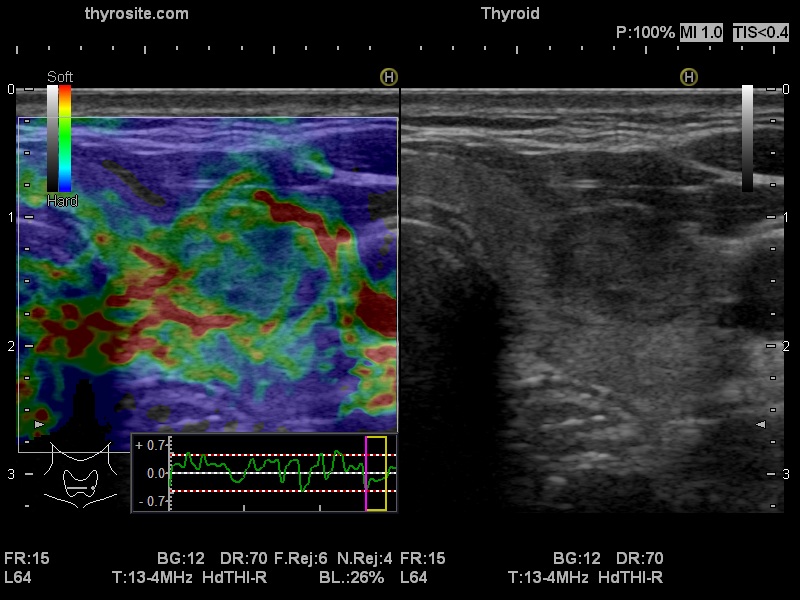

Ultrasonography. The thyroid was echonormal and had multiple minimally/moderately hypoechoic nodules. The lesion in the left lobe was remarkable due to lobulated margins. More than 10 lymph nodes larger than 1 cm in diameter were detected both in the right and the left side of the neck. Some had heterogenous pattern, most of them lacked regular hilum. The vascularity was varied from avascular to obviously irregular.